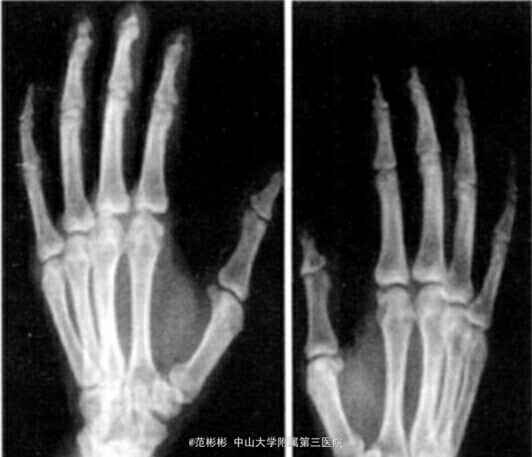

入院检查 :神智清楚,智力正常,头颅外观正常,身高 170 cm,牙齿排列整齐、无脱落。右趾、左第 1~4 足趾、双手手指末梢呈淡粉红色,变形、无压痛。右 趾趾甲畸形,皮肤质硬、皲裂。类风湿因子 (-),抗“ O”试验(-),梅毒抗体 (-),肝、肾功能无异常, 右 指分泌物细菌培养 (-),红细胞沉降率正常,甲状旁腺激素正常。 X 线片检查示:中指,左示、中、无名指末节指骨骨干明显变细、基底部完整 ;右趾远节骨质溶解伴缺失,近节趾骨和趾间关节破坏 ;左 趾、小趾末节部分骨质溶解;全身其余骨质未见异常。